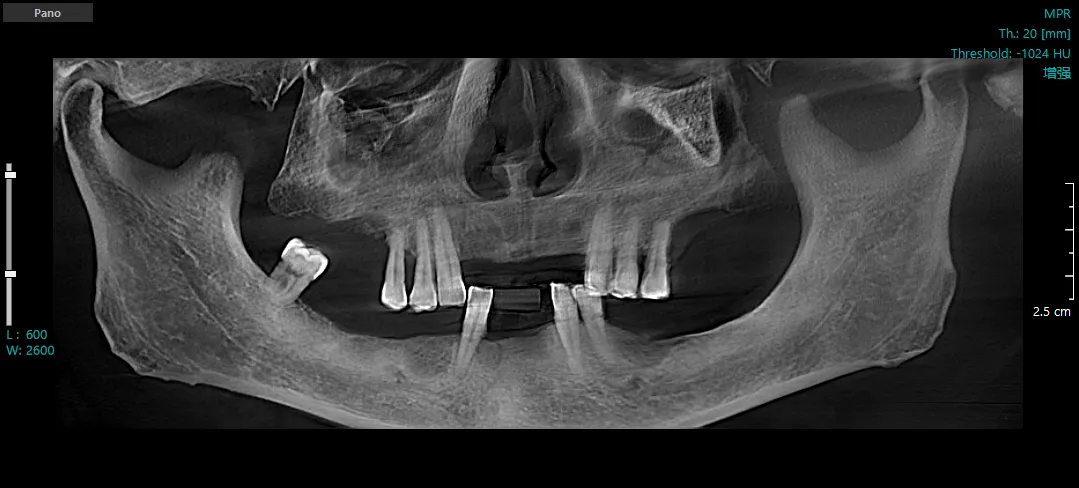

种植前CBCT三维重建图

65岁的张先生,因全口缺牙多年,日常咀嚼功能严重受影响,日前到楼凤网 中医医院口腔科就诊,口腔科主任乐涛检查后发现,张先生口腔基础条件差,牙槽骨吸收严重,这给牙齿修复带来了困难。乐涛凭借着丰富经验和精准操作,通过口腔颌面锥形束CT三维重建技术(CBCT)和口腔3D扫描技术,精准获取了患者口腔的三维模型,掌握了患者口腔血管、神经位置及牙槽骨的吸收情况,并运用种植导板定位技术,成功为张先生种植了11颗前牙,种植成功的当天患者即可正常咀嚼食物。